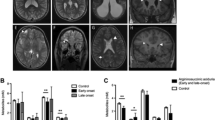

The CSF/plasma glycine ratio was > 0.08 in nine patients and was not available in one patient (patient no: 8) who was diagnosed by metabolic disorders gene panel screening. The median CSF glycine level was 148 (15–320) µmol/L, the median plasma glycine level was 896 (87-1910) µmol/L and the median CSF/plasma glycine ratio was 0.17 (0.09–0.21). In neonatal classic NKH, the median of glycine level was 228 (26–320) µmol/L, the median plasma glycine level was 1468 (159–1910) µmol/L and the median CSF/plasma glycine ratio was 0.19 (0.09–0.21). In infantile classic NKH, the median CSF glycine level was 74 (15–178) µmol/L, the median plasma glycine level was 522 (87–923) µmol/L and the median CSF/plasma glycine ratio was 0.17 (0.14–0.19). Plasma, CSF and CSF/plasma glycine ratio were higher in the neonatal group than the infantile group, but the difference was not statistically significiant (p > 0.05).

Cranial MRI findings were diffuse hypomyelination in 80 % (n: 8/10), corpus callosum dysgenesis in 60 % (n: 6/10), ventricular dilatation in10 % (n: 1/10), hydrocephalus in 10 % (n: 1/10), and mega cisterna magna in 10 % (n: 1/10). Two of the four patients who underwent cranial MRS had a glycine peak (patient no: 2 and 4) but MRS was normal in two patients (patient no: 3 and 9), one of whom had normal plasma glycine level under treatment at the time of MRS acquisition (patient no: 3). EEG findings were multifocal epileptic activity in 100 % (n: 10/10), burst suppression pattern in 70 % (n: 7/10), hypsarrhythmia in 50 % (n: 5/10) and cerebral dysfunction in 20 % (n: 2/10).

Increased levels of CSF glycine are highly indicative of NKH. The lowest CSF glycine found in a patient with classic NKH was 26 µmol/L (normal < 20 µmol/L) in the literature (Van Hove et al. 2002 [updated 2019]; Swanson et al. 2015; Van Hove et al. 2016; Bravo-Alonso et al. 2017). An elevated CSF/plasma glycine level is a further indication of NKH, but is only valid if the CSF glycine level is elevated. Exceptional patients with attenuated NKH have had normal CSF glycine levels, but this is very rare and the sensitivity of elevated CSF glycine is > 99 %, making it the preferred diagnostic test (Van Hove et al. 2016). Similar to the literature, the lowest CSF glycine level (before treatment) was found 26 µmol/L in our patients with homozygous mutations in this study. According to our experience, CSF glycine levels (after excluding pittfalls) was more reliable than CSF/plasma glycine ratio since it can give erroneous results. Therefore, we do not suggest looking at this ratio for a diagnosis, monitoring and/or prognosis especially in patients without elevated CSF glycine levels. In the presence of similar clinical, radiological and electrophysiological findings of NKH, patients with CSF glycine ≥ 25–50 are possible, 50–100 probable and ≥ 100 definitely make you to think diagnosis of NKH, after excluding secondary elevation of CSF glycine. Thereafter GCS activity and/or genetic testing should be made for the exact diagnosis. Prognostic indicators of severe outcome include high CSF glycine level (> 230 µM) and presence of malformations on brain MRI, whereas prognostic indicators of attenuated NKH are low CSF/plasma glycine ratio (< 0.08), late onset (≥ 4 months) and absence of epilepsy were reported (Swanson et al. 2015; Van Hove et al. 2016; Shbarou et al. 2019). However, intrafamilial phenotypic variability was also previously discussed (Shbarou et al. 2019). In this study, although plasma, CSF and CSF/plasma glycine ratio were higher in neonatal group than infantile group, it was not statistically significiant. Mortality ratio was higher in neonatal group than infantile group and being neonatal group was associated severe outcome.